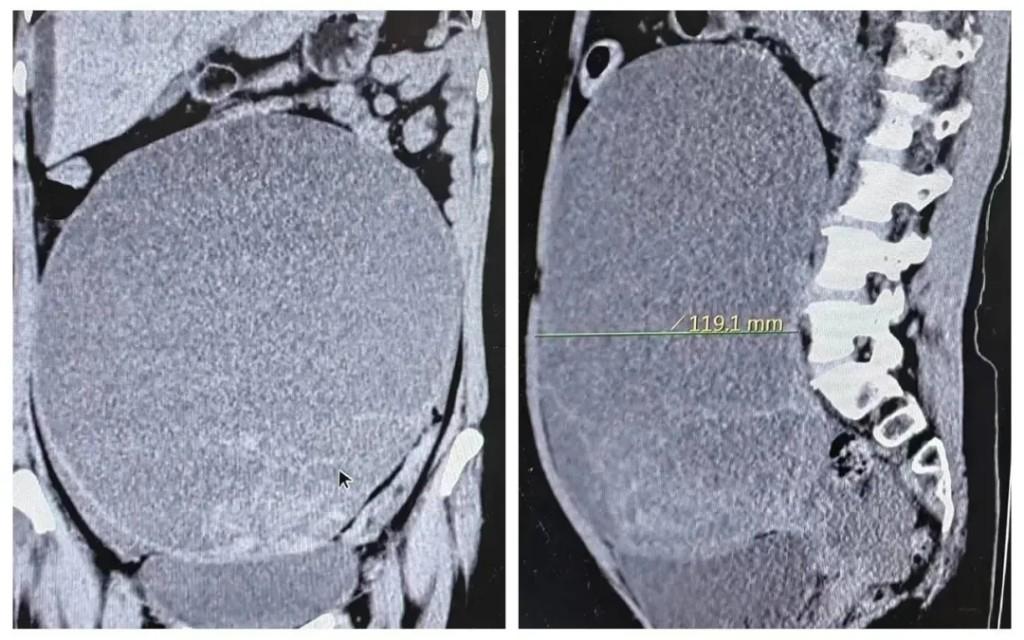

刘女士今年50岁,去年身体开始发胖,但是除了肚子大了一圈并没有其它不适,她以为只是长胖了,并未将此事放在心上。但是短短一个月,她的肚子不断变大,体重在快速增加,可面部及四肢却越发消瘦,刘女士以为是肠胃出了问题,便来长安区医院消化内科就诊。但是检查结果却让所有人大吃一惊,上腹部彩超显示刘女士肚子里的肿瘤已经把整个盆腔和腹腔的脏器全部挤压到了一旁,肿瘤体积巨大,直径更是达到了26厘米。严重压迫了消化道和呼吸道,需要立即入院手术。

术中,刘女士体内巨大的肿瘤压迫了周围组织及器官,杨丽珍主任和陈怡主任严谨细致地将肿瘤与周围正常组织分离开来,且将肿瘤与子宫、双附件以及周边病变组织一并切除。经过三个多个小时的手术,成功拆除了这颗26厘米的炸弹,以及2000ml左右的血性腹水。术后患者生命体征平稳恢复良好,顺利返回病房。